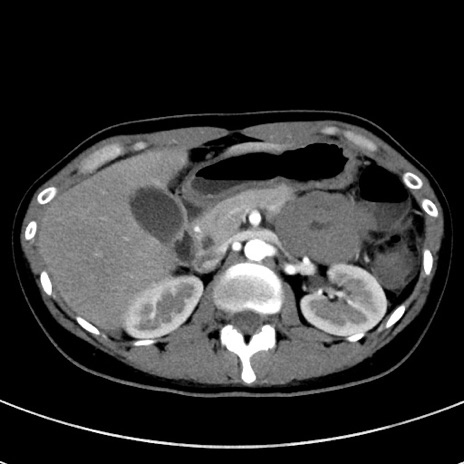

冠状断像

【症例】20歳代女性

【主訴】嘔吐、下腹部痛

【現病歴】昨日夕食後に嘔吐し下腹部痛が出現。本日になっても嘔吐持続し改善しないため来院。

【身体所見】意識清明、BT 37.2℃、BP 108/67mmHg、腹部:平坦、やや硬、下腹部正中から右にかけて圧痛あり、反跳痛軽度あり、tapping pain(+)。

【データ】WBC 13600、CRP 14.94